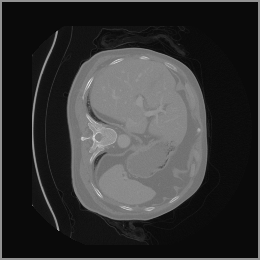

The motivation for this work arises from the need to address these limitations in the synthesis of 3D medical images. Current techniques do not produce high-resolution 3D images that preserve spatial coherence and capture the full complexity of medical data, as shown in Figure 2, 5. The development of advanced 3D generative models tailored specifically for medical imaging could not only improve the quality of synthetic medical images but also help alleviate data scarcity, enhance privacy protection, reduce computational requirement and ultimately advance the use of deep learning in healthcare applications.

To demonstrate the advantages of 3D semantic image synthesis over 2D semantic semantic image synthesis, we conducted a detailed comparison with the SegGuidedDiff [26] model. SegGuidedDiff generates medical images based on 2D semantic maps, producing individual 2D slices that are later stacked to form a 3D image. However, this approach has limitations in capturing spatial continuity and coherence across slices, which is critical for representing the spatial structure of 3D medical images. As a result, inconsistencies often arise between different slices, particularly in preserving anatomical structures across the coronal and sagittal planes. The generated images exhibit varying levels of denoising, resulting in differences in brightness and sharpness across the images. This inconsistency in denoising can lead to noticeable variations in visual quality, where some regions appear clearer and others less distinct.

As shown in Figure 5, the generated slices exhibit high consistency across adjacent slices. The anatomical structures and semantic patterns are smoothly and coherently preserved between slices, indicating that our model is capable of generating 3D-consistent synthetic images rather than isolated 2D slices.